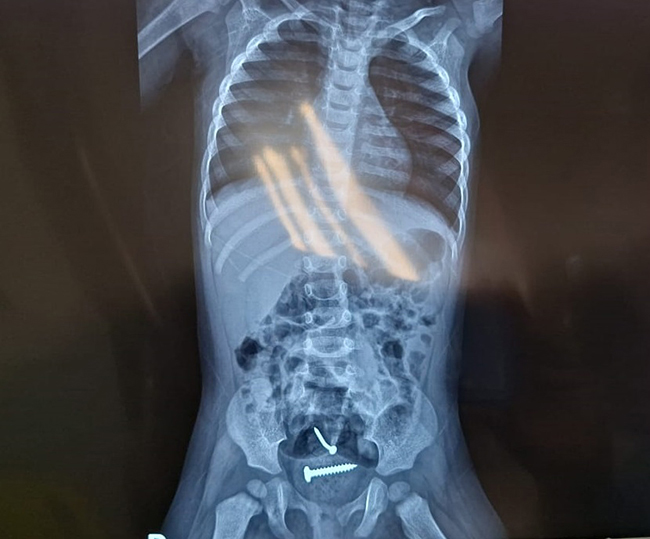

Laudo médico aponta que bebê engoliu parafuso,e não sofreu abuso diz a polícia! Irmã se pronuncia.

Laudo

Laudo médico aponta que bebê de 1 ano não sofreu estupro, diz polícia

A polícia disse ainda que os laudos também apontaram que a criança teria engolido os objetos, que foram expelidos naturalmente, sem necessidade de intervenção cirúrgica.